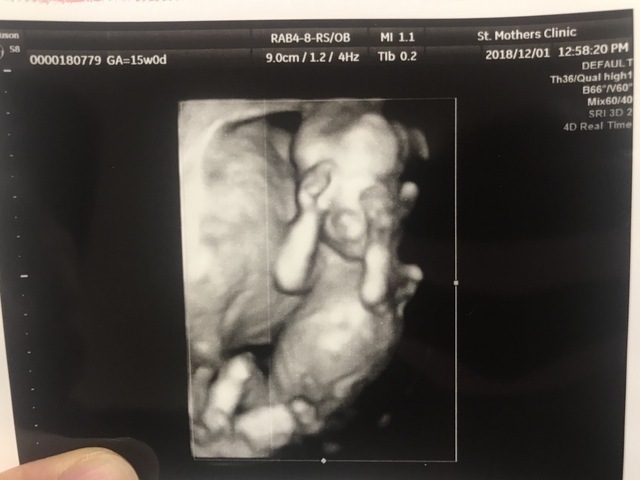

15週0日(15w0d・男の子)|もっきー さん(22歳)

エコー写真撮影時のエピソード:

この頃からポコポコと胎動を感じるようになってとても嬉しかったです。また、初めての腹部エコーでこんな可愛い姿を見れて、メロメロでした。旦那さんとニヤニヤ見つめていました。この手で目を隠してる姿、恥ずかしがり屋な子なのかな?と私に少し似てるのかな?って思ってしまいました。